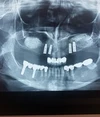

التهاب ما حول الزرعة (الزرعة السنية)

التهاب اللثة حول الزرعة

نقص الأسنان